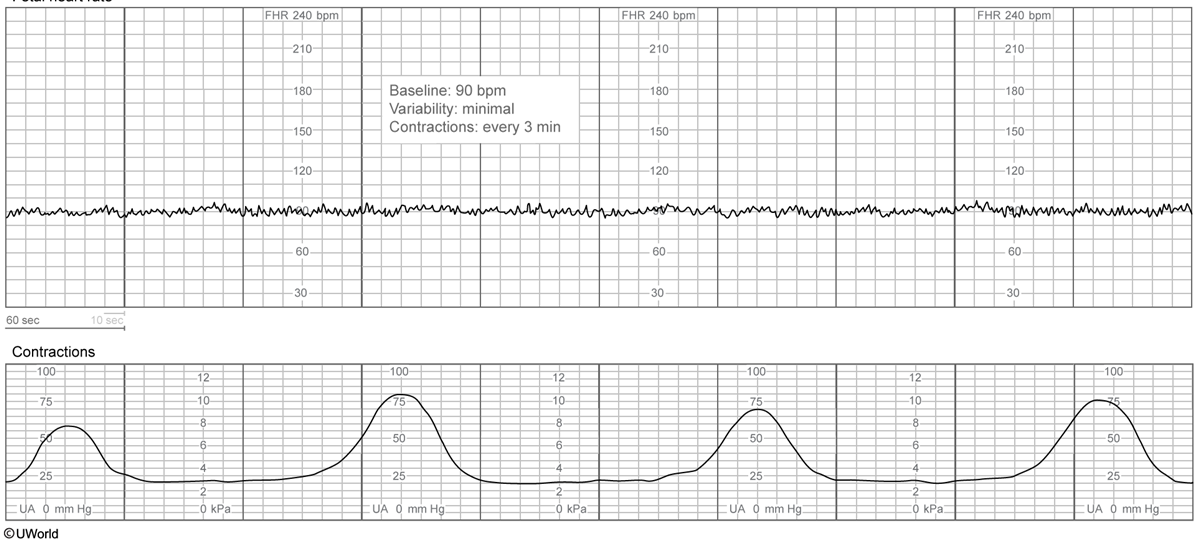

decreased fetal movement & nonpainful but regular contractions, no prenatal care. mother has fatigue, joint stiffness, and erythematous, confluent facial rash

fetal AV block due to mother’s lupus